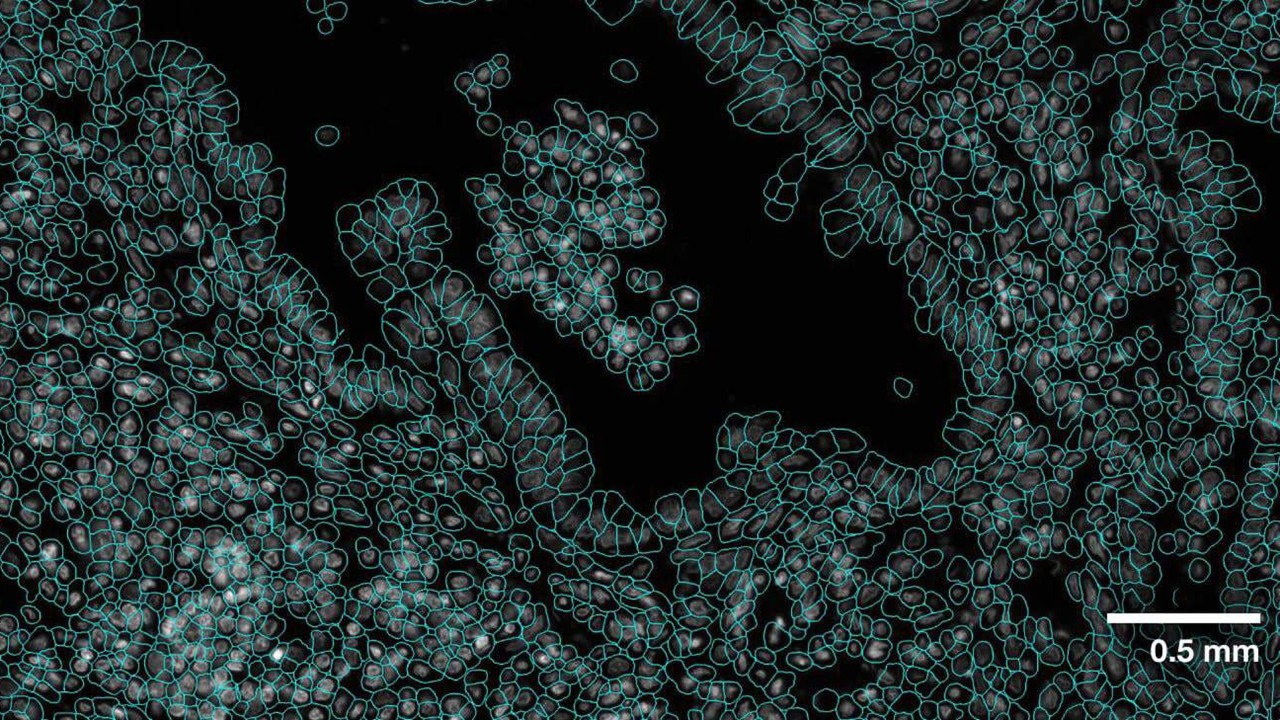

• 借助 NVIDIA AI 基础模型 VISTA-2D 使用生成式 AI 进行高精度细胞分割。

• 利用 cuCIM 为空间的加速图像处理和数据加载,并利用 RAPIDS 单细胞分析空间的转录组学方面。

• 在空间的分析中使用 NVIDIA GPU,以降低处理大量空间数据的分析时间。

使用 CosMx Whole Transcriptome 面板绘制的人脑海马体图像(将于 2025 年上市)。 图片由 Bruker Spatial Biology 提供。